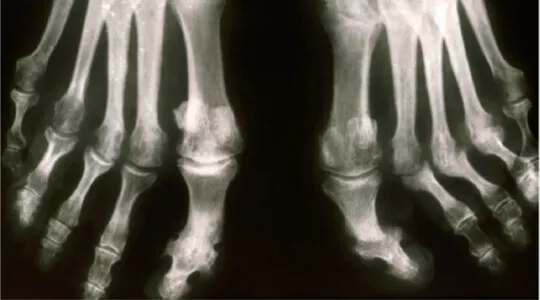

Artritis psoriatica

Artritis psoriatica - Gewrichtsontstekingen